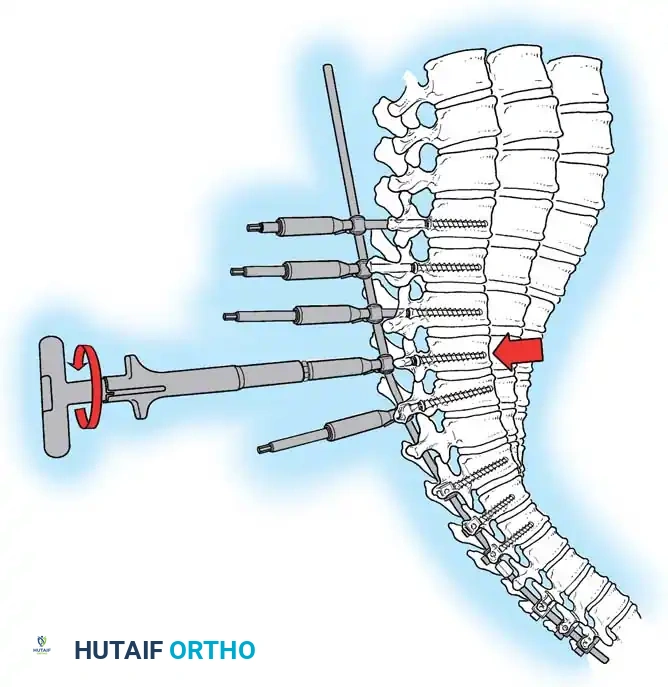

Diagram illustrating the placement of pedicle screws and the site of posterior column osteotomies.

3. Pedicle Screw Instrumentation

Free-hand or navigation-assisted pedicle screws are placed bilaterally. High implant density is crucial at the apex (to allow for powerful reduction forces) and at the cranial and caudal foundations (to prevent pullout).

The reduction is achieved via a cantilever maneuver. The rods are seated in the distal foundation screws first. Using reduction tubes and set screws, the rod is sequentially drawn into the apical and proximal screws. This maneuver translates the spine to the rod, simultaneously correcting the kyphosis and restoring sagittal balance.

Cantilever reduction maneuver closing the posterior osteotomies and correcting the kyphotic deformity.

5. Apical Compression

Once the rods are seated, sequential compression is applied across the apical screws. This closes the Ponte osteotomies, shortens the posterior column, and acts as a fulcrum to lengthen the anterior column, effectively reversing the biomechanical pathology of Scheuermann disease.